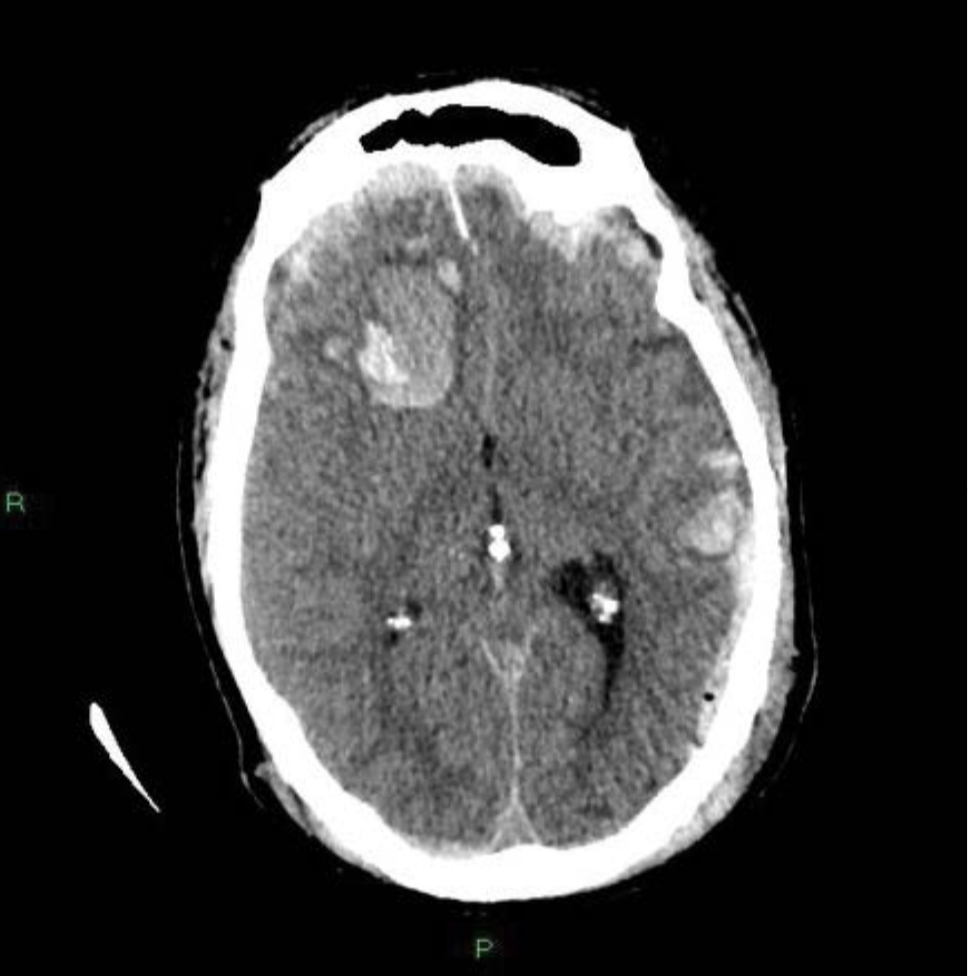

•腦內血腫/腦積血:人腦是密閉空間,若頭部撞擊引發腦出血,腦內積血會令顱內壓上升,造成顱內高壓,傷者事後或會神智不清。

長者腦部日漸萎縮,與頭骨之間容易產生虛位。頭部創傷即使僅屬輕度或中度,腦內積聚的瘀血再少,亦會被身體吸收而化為血水,有機會在意外後約一至六個月內不斷膨脹,最終導致慢性硬膜下出血。患者反應會變得遲緩,步履不穩,嚴重者甚至會出現偏癱,建議立即求醫,接受腦掃描檢查。

傷者求醫時,醫生會先觀察相關臨床症狀,如言語不清等。如有需要,病人可接受電腦掃描或磁力共振,了解傷者顱骨受損程度,以及是否出現腦出血等。

治療方面,以硬膜下出血為例,神經外科專科醫生會以手術處理積血引起的徵狀,先在頭骨鑽孔,再揭開頭骨,放出血水。

腦外科手術主要適用於嚴重腦創傷,例如以開顱手術抽出腦內瘀血,令顱內壓回復正常水平。如顱內壓上升是腦腫脹所致,醫生可施行去骨瓣減壓手術,打開頭皮及頭骨,取走部分頭骨後僅縫上頭皮,於腦內騰出空間以紓緩壓力,減低顱內壓。